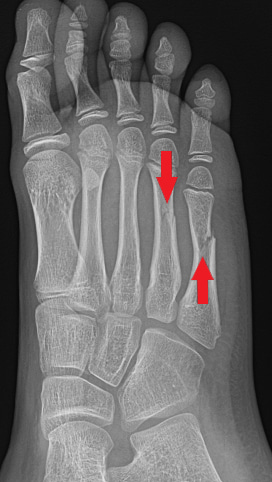

Example of a foot fracture

Example of a toe fracture